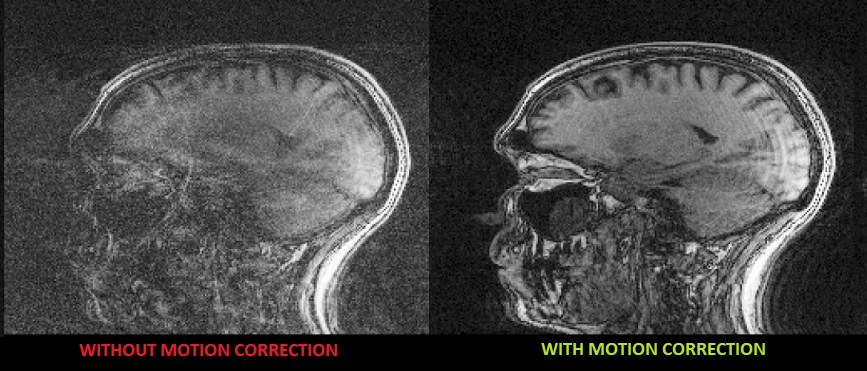

Motion during scan induces image quality degradation (blurred images, motion "ghost" artifacts) to a degree that may require repetition of the scan. The sensitivity to motion increases with newer imaging like functional and diffusional MRI and with higher resolution scanners. As 20-30% of all scans are affected by motion, the direct annual financial burden of motion artifacts, due to the need to repeat scans, is estimated at $1 Billion in the USA alone.

The EndoScout system has been intensively evaluated for motion tracking, aiming to eliminate the effect of motion on diagnostic imaging. Many of the diagnostic scans are adversely affected by subject motion, including scans of children, non-cooperative adults, and new modalities like functional and diffusion MRI that are sensitive even to a minimal level of motion like tremor. The sensitivity of MRI to motion requires many of the scans in small children and in non-cooperative adults to be conducted under sedation or anesthesia, which doubles and triples the cost of the diagnostic study, and involves substantial risks. Ongoing clinical studies of motion artifact elimination using the EndoScout tracking system are conducted at the Massachusetts General Hospital and at the Boston Children’s Hospital in Boston.

The following image was taken from the abstract: Retrospective correction of head motion using measurements from an electromagnetic tracker. It shows substantialy lower artifact levels in image B where retrospective motion correction was used vs image A which is the uncorrected image. Images C and D are zoomed in areas of A and B respectively. Image D shows reduced blurring and improved gray/white matter differentiation.